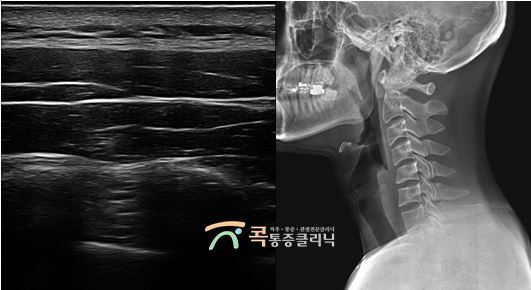

경추성 두통과 목디스크 30대 여성 환자분

3.jpg

고개를 들기 어려울 정도로 심한 목과 어깨 통증이 찾아오셨던 환자분이셨습니다. 통증이 매우 심하여 응급실까지 다녀오셨고, 뇌 MRI 등을 시행하였을 때 이상 소견이 없으셔서 병원을 내원하셨습니다. 내원 당시 목을 조금만 움직이려 해도 통증이 심하다고 하셨고, 목 뒤쪽으로 느껴지는 두통이 심해서 불면증까지 있으셨습니다.

4.jpg

진단을 하니 환자분께는 경추 5-6번 협착증과 경추 4-5번 추간판 탈출증이 발견되었습니다. 이로 인해 신경 압박이 있었던 것이고, 두통이 생긴 것이었기에 목디스크 주사치료를 시행하였습니다. 치료 이후 현재는 많이 호전되셔서 고개를 들었을 때도 통증이 적어지셨고, 두통도 호전되어서 잔여 통증과 재발 방지를 위하여 도수치료를 시행하고 있습니다.